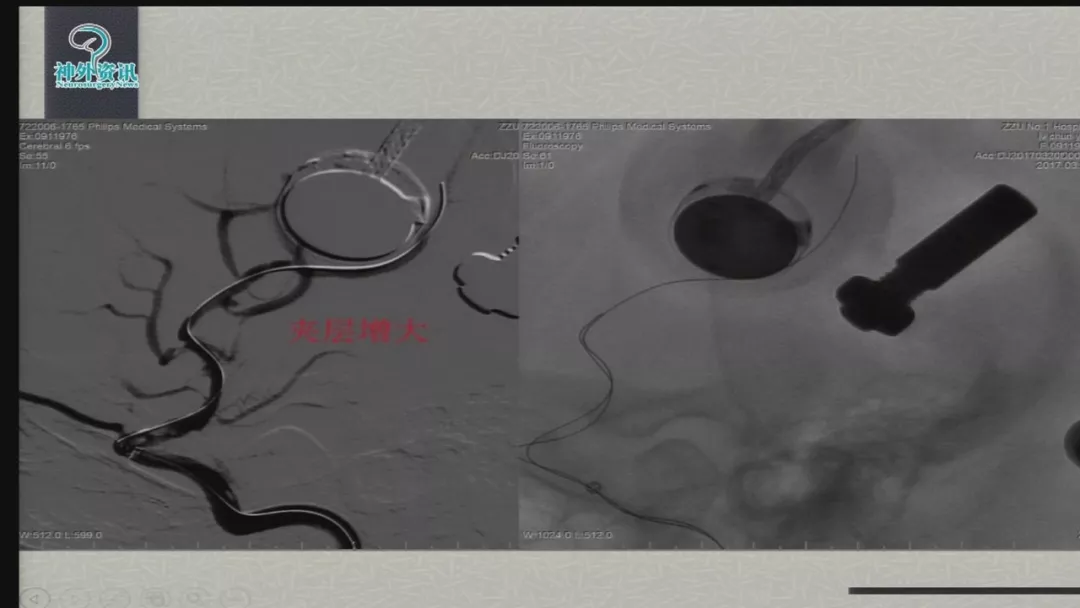

今天为大家分享的是由郑大一附院徐浩文教授在第七届全国介入医学工程大会上带来的“Neuroform EZ在ICAD治疗中的应用”精彩讲课视频和PPT,欢迎观看!(内容未经讲者审核,不当之处请与我们联系)